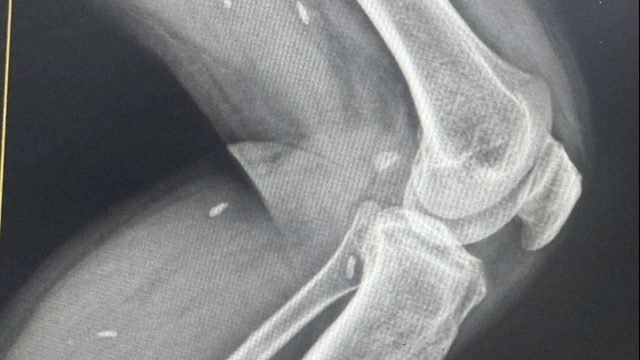

| Nữ bệnh nhân đã bị cháy da sau điều trị tại Thẩm mỹ Viện Quốc tế Venus |

Sau 1 buổi được cơ sở bắn laser kết hợp với bôi tế bào gốc, chị Hồng V. trở về nhà trong tình trạng đỏ rát khắp các vùng da vừa chăm sóc, đứng ngồi đều khó khăn, vùng da đen sạm. Lo lắng, chị kiểm tra lại chai serum tế bào gốc thì tá hỏa phát hiện sản phẩm không có nguồn gốc xuất xứ, không phiếu công bố sản phẩm. Tiếp tục tìm hiểu thông tin, bệnh nhân phát hiện người trực tiếp điều trị cho mình không có chứng chỉ hành nghề.